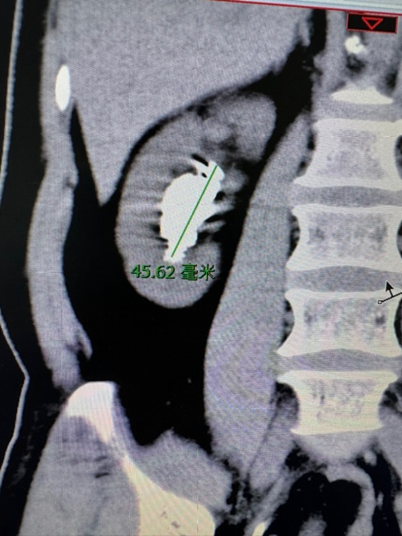

术前CT检查